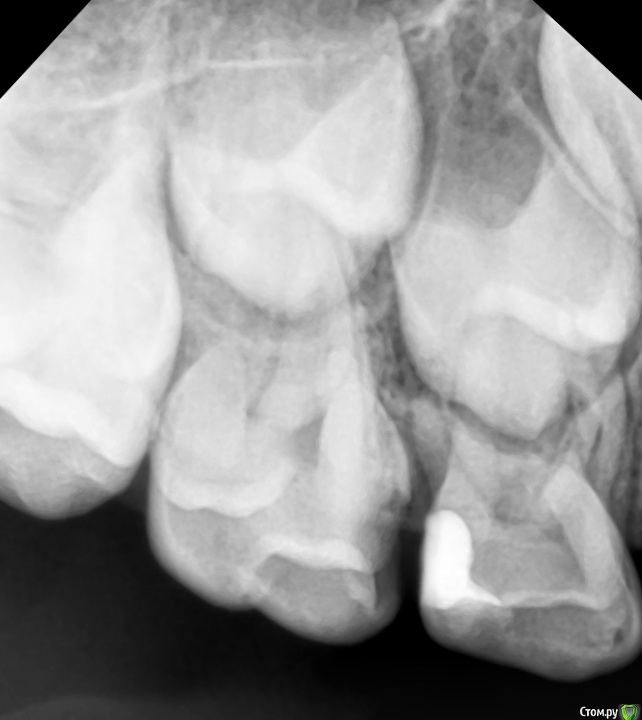

CRAZYDUCK Опубликовано 5 июня, 2018 Автор Поделиться Опубликовано 5 июня, 2018 Про эктопию верхних 6 зубов ( импактные шестые зубы). Встречается не так уж и редко . Для общего развития всем будет полезно . Эктопия ( импактные верхние 6 зубы).просто говоря - верхние 6 зубы из-за дефицита места на верхней челюсти или из-за оси прорезывания направленной медиально , способствуют резорбции корня 6.5 или 5.5. Эктопия может быть обратимой и необратимой . Но после 8 лет ( но возраст зубной может отличаться от антропометрического, поэтому смотрим на сроки прорезывания других постоянных зубов у конкретного ребёнка ) ортодонтическая коррекция нужна ( процесс необратимый). Методы устранения -Без удаления временного 5 возможно применение частичной брекет-системы , которая нормализует ось прорезывания 6 зуба ( в литературе можете найти всякие латунные сепараторы , но это история и мне кажется сложнее брекет-системы ). На первых двух фото показан случай эктопии 1.6 , который не требует удаления 5.5 . А вот дальше показан случай эктопии 2.6 , требующий удаления 6.5. Каждый случай индивидуален . ‼️коллеги , важно помнить , что 2.6 в случае удаления 6.5 полностью заблокирует зачаток 2.5 ‼️здесь обязательно нужна будет помощь ортодонта ( немедленная или отсроченная ортодонт с родителями решат ). Ну а 5 временные зубы после такой подлости со стороны шестёрок могут быть причиной воспаления ( хотя сами пятые могут быть инактными ). 2 Ссылка на комментарий

CRAZYDUCK Опубликовано 5 июня, 2018 Автор Поделиться Опубликовано 5 июня, 2018 (изменено) Про эктопию верхних 6 зубов . Изменено 5 июня, 2018 пользователем CRAZYDUCK Ссылка на комментарий